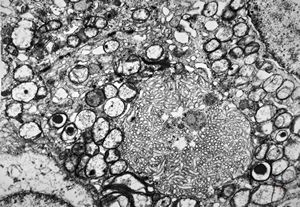

F,3y. | toxoplasmosis